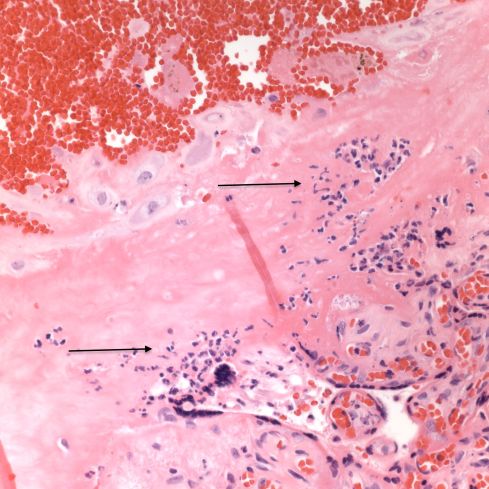

I regret not having explored and recorded more of the vascular anatomy in the uteri that I examined. The focus was on the diagnostic features of accreta, or possible causes of atony. One incidental observation that I could not explain in a uterus removed for placenta accreta was severe chronic inflammation in a deep myometrial artery in which a portion of the artery was necrotic suggesting trophoblastic remodeling (Figs 5a, 5b).

Fig 5a: The artery in the center is surrounded by large gravid myometrial myocytes. Its wall on the right is intact, but the left, top and bottom shows loss of medial smooth muscle, numerous inflammatory cells, and smudged eosinophilic material in the media. H&E 10x

Fig 5b: This image is a higher magnification of the above artery at the junction of intact and damaged media. The inflammatory cells appear to include neutrophils, lymphocytes and even plasma cells. H&E 40x